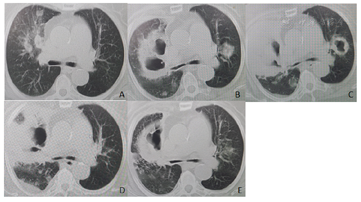

2022年9月20日,血常规+CRP:白细胞计数9.08×109/L,中性粒细胞8.01×109/L,血红蛋白98 g/L,C反应蛋白286.31 mg/L;呼吸道13种病原体检测:铜绿假单胞菌阳性;G试验和GM试验均为阴性。2022年9月22日,支气管镜检查:右肺上叶前段支气管新生物阻塞,双肺支气管炎性改变(图2A)。BALF给予活检并送mNGS检查:铜绿假单胞菌、代尔根霉、烟曲霉、EB病毒、人疱疹病毒1。病理结果:黏膜重度慢性炎,BALF未见肿瘤细胞。肺泡灌洗液真菌培养:烟曲霉;肺泡灌洗液细菌培养:耐药铜绿假单胞菌。复查CT示双肺多发空洞,考虑脓胸并空洞形成,较2022年9月19日CT片加重(图1B),给予哌拉西林钠他唑巴坦钠4.5 g 2次/d静滴联合伏立康唑0.2 g 2次/d静滴治疗3 d后患者仍有低热,伴咳嗽、咳痰、咯血,炎症指标改善不明显,调整抗生素为:伏立康唑0.2 g 2次/d静滴(2022年9月24日-2022年10月9日)、美罗培南1 g tid静滴(2022年9月27日-2022年10月14日)、硫酸阿米卡星0.8 g 1次/d静滴(2022年9月29日-2022年10月3日)。复查CT示双肺多发空洞,较2022年9月24日CT片右肺病变范围增多(图1C)。遂予以结合药敏给予加用两性霉素B胆固醇硫酸酯体2 mg(50~200 mg)泵入及两性霉素B 5mg 2次/日雾化(2022年9月29日-2022年10月10日)抗感染治疗辅以地塞米松3 mg 1次/d静脉注射激素抗炎。考虑患者感染重,治疗难度大,院内组织多学科讨论后,先后行气管镜下两性霉素B局部注射治疗3次。患者症状和氧合逐渐改善,复查CT示双肺多发实性密度并空洞,局部伴气液平,空洞较前缩小,双肺部分斑片影新增(图1D)。10月11日CT示双肺多发实变并空洞,局部伴气液平,较2022年10月4日CT吸收好转较(图1E)。复查气管镜示右中叶管口较前改善(图2B)。治疗期间多次复查曲霉感染相关指标:曲霉菌IgG抗体均<31.25 AU/ml;曲霉半乳甘露聚糖测定均<0.499。

综上所述,糖尿病患者因细胞免疫功能低下,易合并真菌感染,其临床症状、影像学特异性差,支气管镜下表现相对特异,mNGS极大地提高了病原体的检测能力。因此当患者合并社区获得性肺炎且广谱抗生素治疗无反应时,应仔细询问其职业、生活接触史。曲霉菌感染初始治疗无效或不正规治疗是发生大咯血的危险因素,一旦并发严重咯血甚至大咯血治疗效果极差,治疗重在早防,及时进行支气管镜检查、病理检查及mNGS等尽早明确诊断,确诊后尽早足量足疗程使用广谱有效抗真菌药物。确诊肺部真菌感染的同时,还应注意排查鼻窦,颅内等其他部位的真菌感染。确诊侵袭性肺曲霉菌病后,要注意强化血糖控制,加强营养支持治疗,应用有效的抗真菌药物且疗程应足够长,部分肿瘤标志物在急性感染期会异常升高,但感染控制后可明显下降,应注意监测,以除外恶性肿瘤。